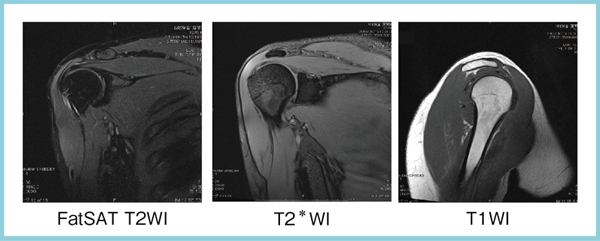

関節のMRI 第3版 | 上谷雅孝, 青木隆敏, 神島 保, 江原 茂, 杉本。肩関節のMRI−読影ポイントと新しい知見−第3版 | 佐志 隆士。その他検査(関節・軟骨) 肩MRI | AIC八重洲クリニック。ホテイ やきとり缶詰 岩下の新生姜入りしょうが味 70g×9缶セット 非常食。【裁断済】\r肩関節のMRI 改訂第3版\r佐志隆士、秋田恵一 編集\rメジカルビュー社\r\r・こちらで購入させて頂いたものです。\r・裁断済みです。そのため、状態は悪いとしています。\r 裁断済みの意味が分かる方のみ、ご購入をお願いいたします。\r・書き込み、マーカーはないと思いますが、確認漏れがあった場合はご容赦ください。\r・スキャン後ですので、多少のヨレやローラー痕がある可能性があります。ご理解の上ご購入をお願いいたします。\r・即購入OKです。\r 恐れ入りますが、値下げ交渉はご遠慮下さい。。肩関節脱臼に対する治療 | 長野整形外科クリニック。その他検査(関節・軟骨) 肩MRI | AIC八重洲クリニック。m3電子書籍 | 関節外科 2022年11月号 Vol.41 No.11 腱板断裂治療。肩関節疾患 | ならやまと整形外科 スポーツクリニック。肩関節(MRI): 正常解剖学 | e-Anatomy。肩関節脱臼|SPORTS MEDICINE LIBRARY|ザムスト(ZAMST)。Open Bore 3T MRIと320列面検出器CTの最新臨床応用 Toshiba 3T。肩関節(MRI): 正常解剖学 | e-Anatomy。プライマリケア医にとってMRIは、確定診断をサポートするための